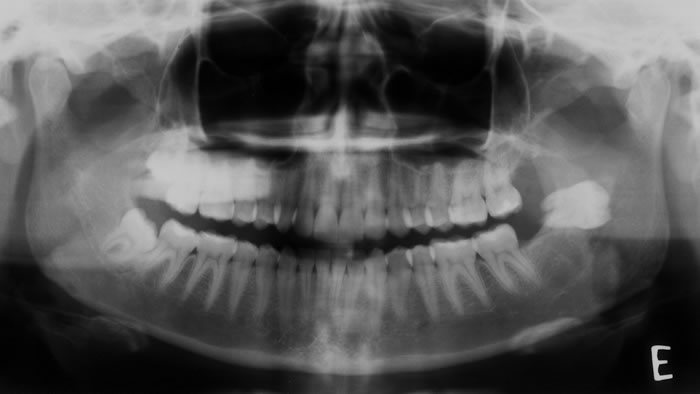

Caso2: Localização de dente retido

História clínica de exodontia do dente 38 há um ano, sem no entanto localizar o elemento dentário acreditando que o paciente havia engolido o dente. Na radiografia panorâmica observa-se a presença do dente 38 superposto ao ramo. Na tomografia localiza-se o dente no assoalho bucal.